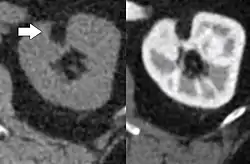

- CT scan of a renal angiomyolipoma. It involves the renal cortex, and has an attenuation of less than 20 HU on the Hounsfield scale, which are typical characteristics.[8]